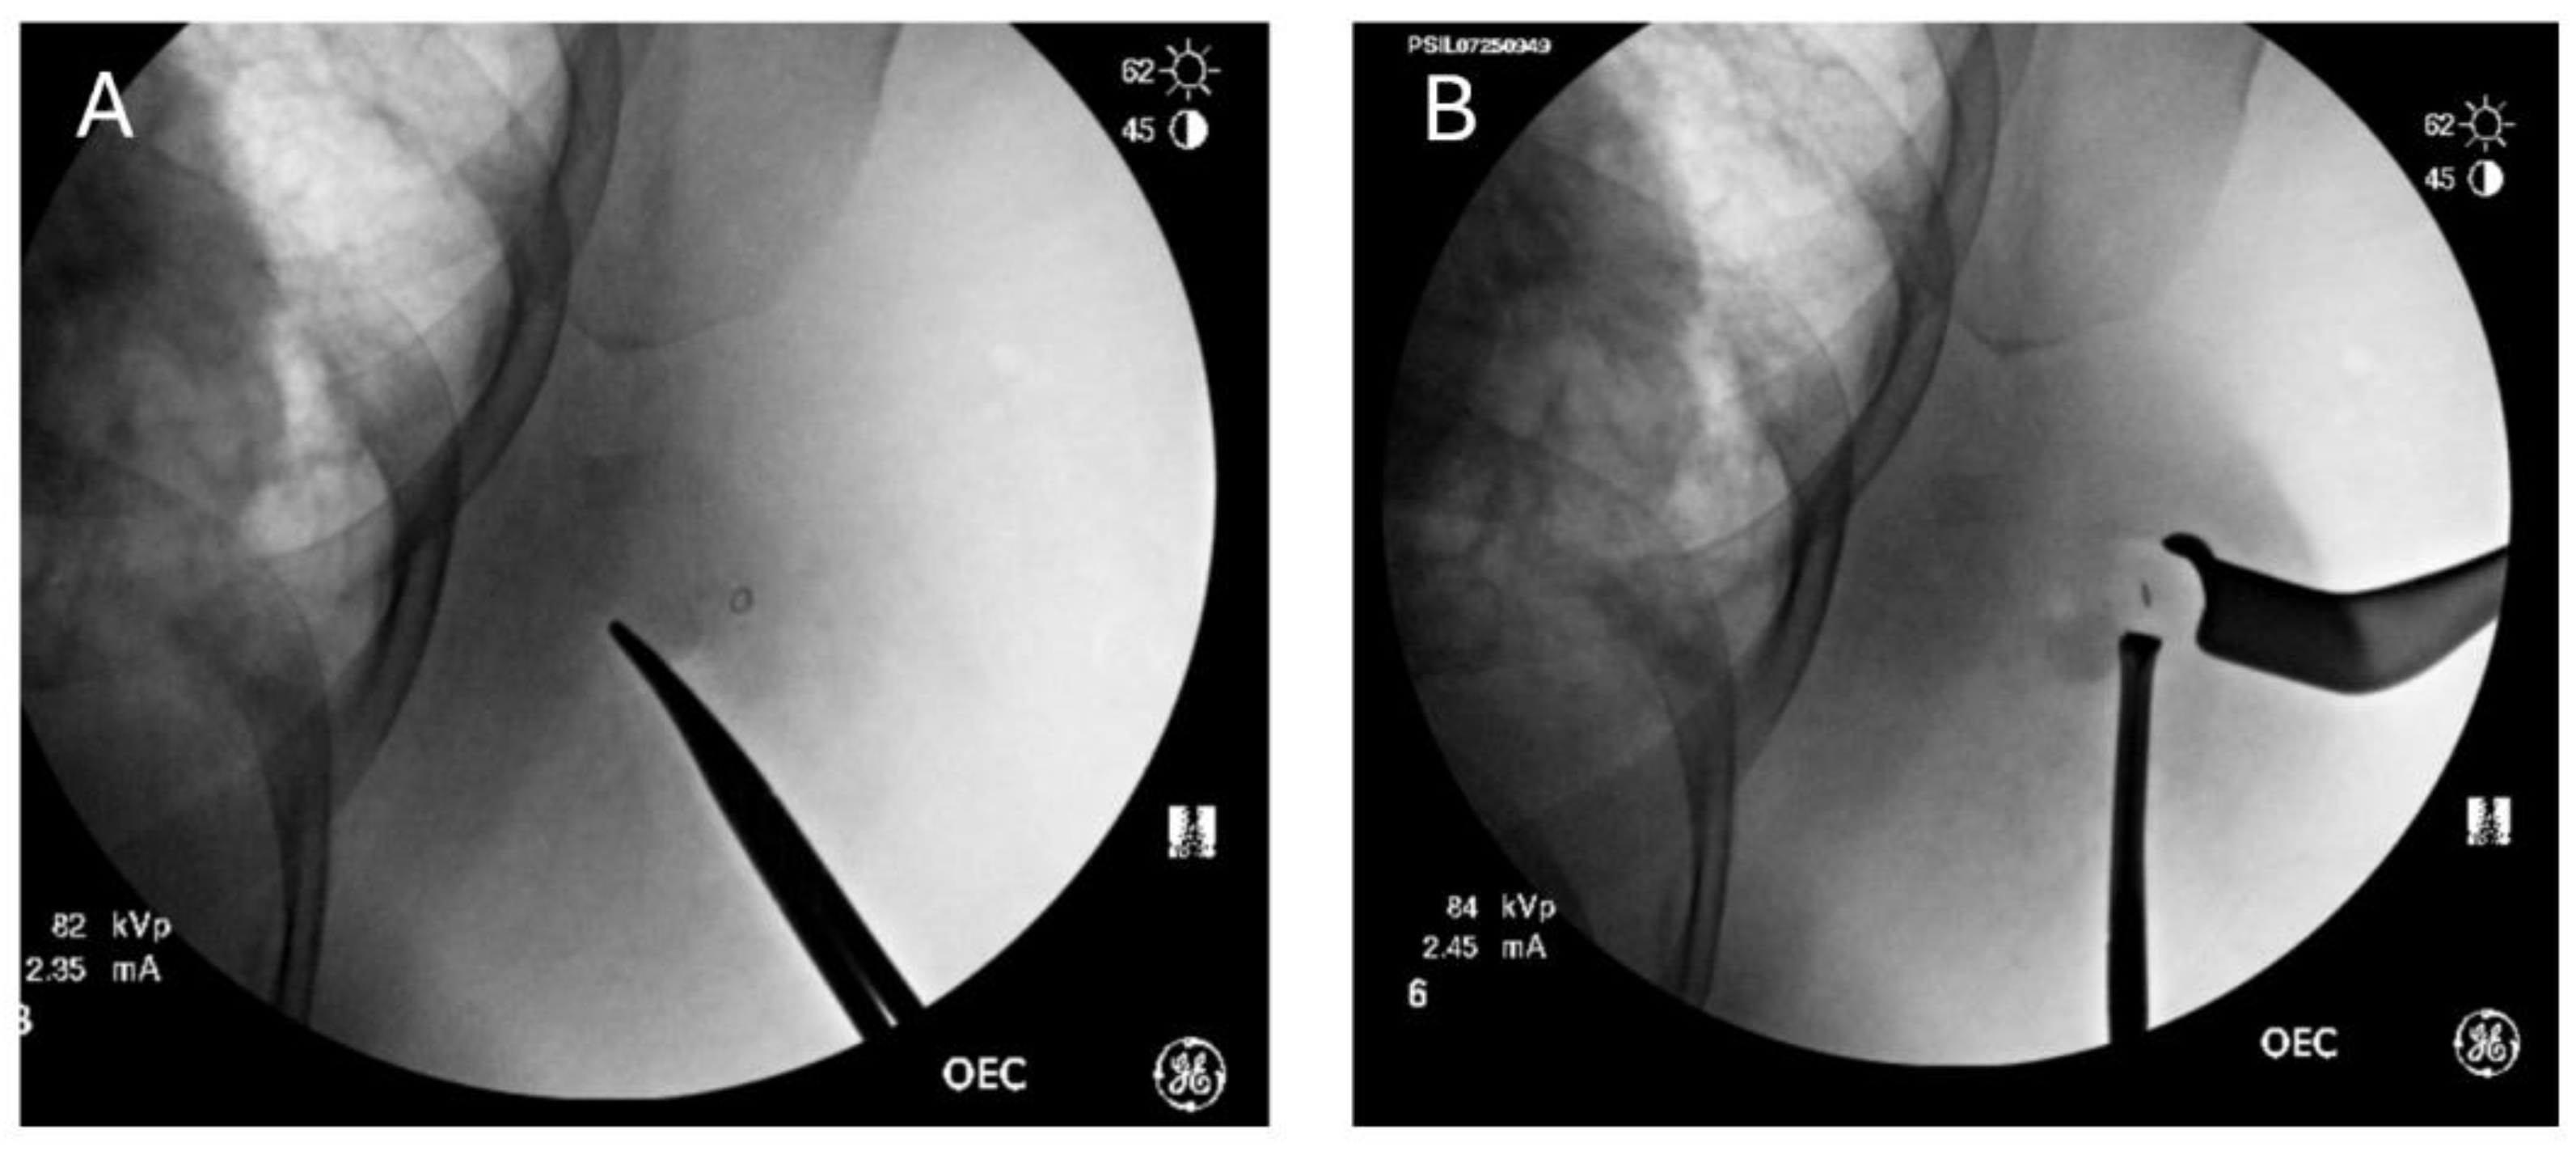

- Weiser, R., Manno, G. C., Cass, S. H., Chen, L., Kuo, Y. F., He, J., Robinson, A. S., Posleman Monetto, F., Silva, H. C., & Klimberg, V. S. (2023). Fluoroscopic Intraoperative Breast Neoplasm and Node Detection. Journal of the American College of Surgeons, 236(4). [CrossRef]